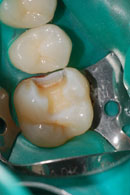

Das Komposit wird anschliessend schichtweise in die Kavität eingebracht und erneut mit Blaulicht ausgehärtet. Dies verhindert die Bildung von Randspalten infolge der unvermeidlichen Polymerisationsschrumpfung des Kunststoffes. Anschliessend erfolgt das Ausarbeiten und Polieren der Füllung.

Aufgrund der oben genannten Schrumpfung sollte man das Legen von zu grossen Kunststoffüllungen vermeiden. Grosse Defekte werden mit laborgefertigten keramischen Inlays versorgt